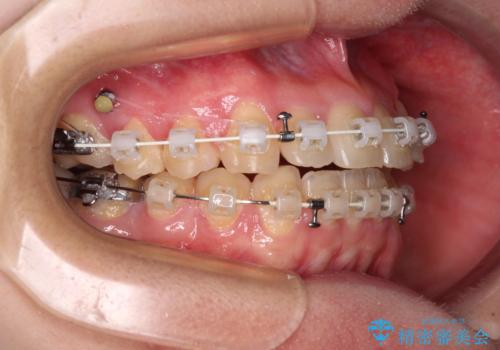

診査を行ったところ、下顎前歯が1本欠損しており、下顎歯列が上顎よりも小さくなっていることで、上顎にデコボコが生じていました。

口元を見ると抜歯をして突出感を改善するような状態ではなかったため、上顎歯列のデコボコを整えて、歯列全体を後方に移動させることでバランスを取ることとしました。

マウスピース矯正は自己管理が煩わしいとのことで、ワイヤー装置にて矯正治療を行うこととしました。

思っていた以上に上顎歯列を後方に移動させることができ、すっきりとした口元に仕上げることができました。